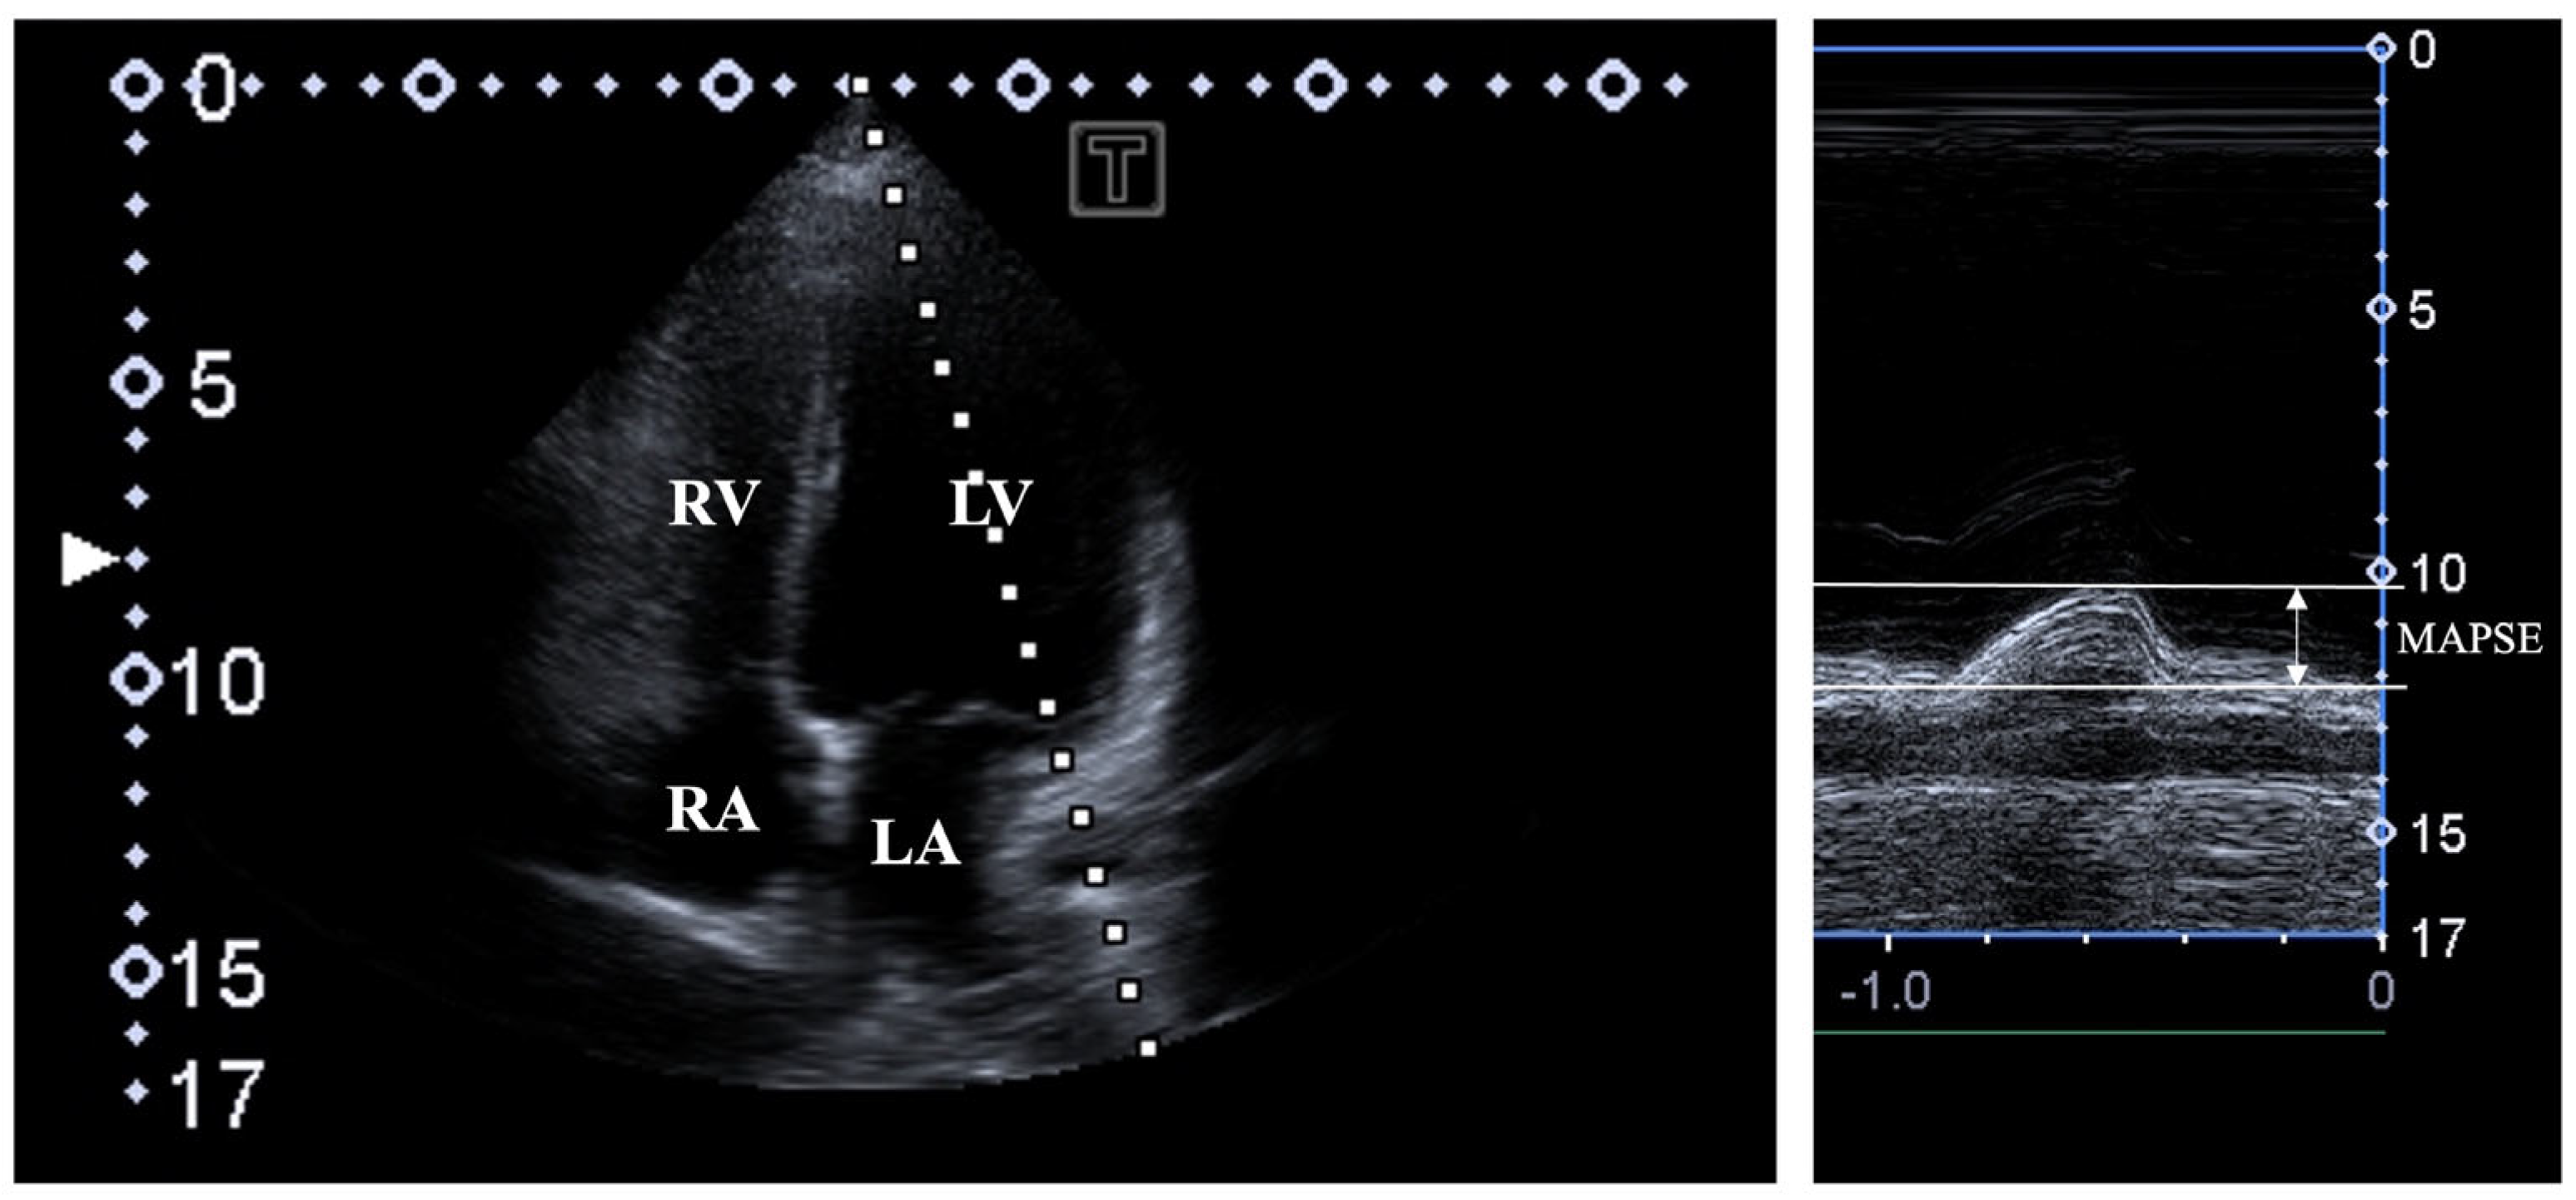

Two-dimensional Doppler echocardiography. A Toshiba ArtidaTM cardiac ultrasound device (Toshiba Medical Systems, Tokyo, Japan) was used in all tests attached to a PST-30BT (1–5 MHz) phased-array transducer. In all individuals being in the left lateral decubitus position, the transducer was placed on their chest in typical parasternal and apical positions by the observer. In all cases, LA and LV were quantified, and Simpsons’s LV-EF measurement was carried out. Significant valvular stenosis and regurgitation were excluded by Doppler echocardiography. LV diastolic function was assessed by measuring transmitral flow E and A velocities and their ratio by pulsed Doppler. MAPSE was measured in the apical long-axis view as the movement of the lateral MA edge towards the apex of the LV in systole by MME (Figure 1) [2].

Figure 1.

Assessment of mitral annular plane systolic excursion (MAPSE) by M-mode echocardiography in apical four-chamber view. Abbreviations: LA = left atrium; LV = left ventricle; RA = right atrium; RV = right ventricle; MAPSE = mitral annular plane systolic excursion.